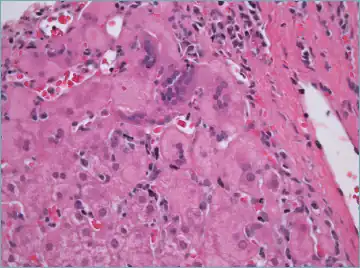

| Micrograph showing a lymphoplasmacytic interface hepatitis—the characteristic finding of autoimmune hepatitis. Liver biopsy. H&E stain. | |

Histological features supportive of a diagnosis of autoimmune hepatitis include:[10]

- A mixed inflammatory infiltrate centered on the portal tract

- The inflammatory infiltrate may breach the interface between the portal tract and liver parenchyma: so-called interface hepatitis

- The most numerous cell in the infiltrate is the CD4-positive T cell.

- Plasma cells may be present within the infiltrate. These are predominantly IgG-secreting.

- Eosinophils may be present within the infiltrate.

- Emperipolesis, where there is penetration of one cell through another, within the inflammatory infiltrate

- Varying degrees of necrosis of periportal hepatocytes.

- In more severe cases, necrosis may become confluent with necrotic bridges forming between central veins.

- Hepatocyte apoptosis manifest as acidophils or apoptotic bodies.

- Rosettes of regenerating hepatocytes.

- Any degree of fibrosis from none to advanced cirrhosis

- Biliary inflammation without destruction of biliary epithelial cells in a minority of cases.